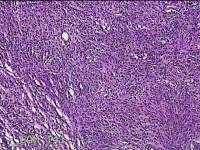

右拇指包块

性别

男

年龄

35岁

临床诊断

右拇指包块性质待查

一般病史

发现右拇指肿物半年。

标本名称

大体所见

灰白暗红色包块2.5x2x0.8cm一个,表面光滑,切开包块呈实性,切面灰白粉红色,质软。

良性病变。